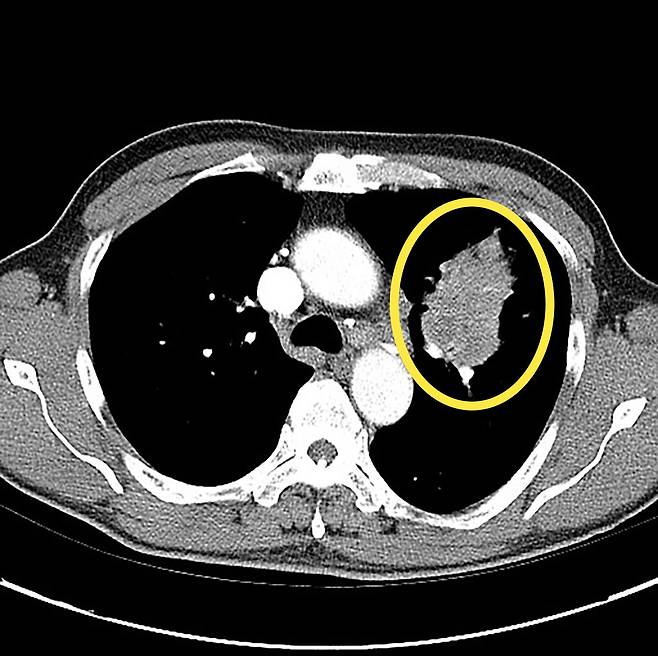

56세 여성 이모 씨는 평소 담배를 피운 적이 없고 기침, 흉통과 같은 호흡기 증상도 없었다. 어느 날 소화가 잘 되지 않고, 상복부 불편감이 지속돼 병원을 찾아 복부 CT 검사를 받았다.

검사 결과 위나 간에 큰 이상이 없었지만 영상 판독 과정에서 폐 하부에 작은 결절이 우연히 발견됐다. 의료진은 추가로 흉부 CT 검사를 시행했고, 정밀 검사 결과 초기 폐암이 의심돼 수술을 진행했다. 다행히 암이 초기 단계에서 발견돼 최소 침습 수술만으로 제거할 수 있었고 현재는 항암치료 없이 정기 추적 관찰을 받고 있다.